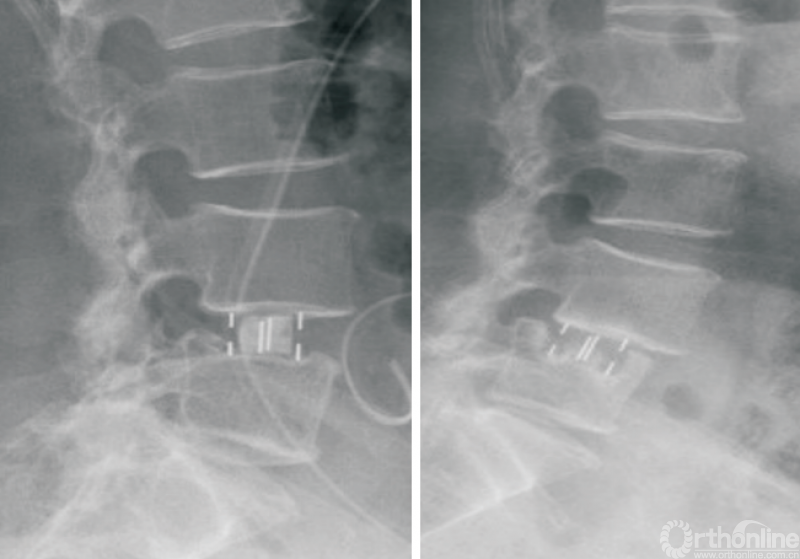

OLIF联合后路固定(1)是治疗脊柱滑脱等失稳性疾病的经典方式[5-9],在有效减压、恢复脊柱稳定性的同时,可以避免后方肌肉、韧带等结构的损伤。相关的研究对比OLIF以及经椎间孔入路腰椎椎间融合术(transforaminal lumbar interbody fusion,TLIF)手术治疗退行性腰椎滑脱,结果表明,两者在改善术后疼痛等方面没有明显差异,且具有住院时间短、出血量少、术后腰痛较轻等特点[10-12]

图1 经典的OLIF

CHUNG等[13]的研究表明,相较于前入路腰椎椎间融合术(anterior lumbar interbody fusion,ALIF)手术,OLIF在恢复椎间隙高度及节段前凸方面更加具有优势;葛腾辉等[14]研究证实,OLIF联合后路固定治疗退行性腰椎滑脱能进一步减少腰椎退行性滑脱患者的滑移率,并增加手术节段前凸角度。

俞仲翔等[6]研究证实,对于邻椎病的治疗,OLIF可以取得与后路腰椎椎间融合术(posterior lumbar interbody fusion,PLIF)等经典手术方式同样的效果,且能够缩短手术时间,减少并发症的发生。王志强等[15]研究证实,OLIF联合单侧或双侧的椎弓根螺钉固定均可有效治疗腰椎退行性疾病。CHO等[16]研究表明,对于存在矢状位失衡的退行性脊柱侧弯患者,OLIF联合后路螺钉治疗比传统的PLIF更加有效。因此,经典的OLIF技术可以应用于脊柱侧弯、脊柱滑脱、腰椎椎管狭窄等众多腰椎退行性疾病的诊疗。